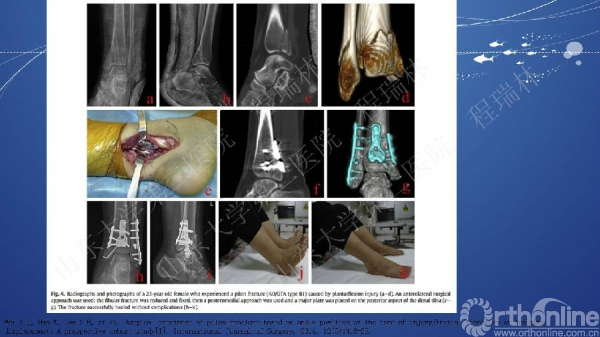

Pilon骨折的手术基本原则

Pilon骨折是踝部的复杂骨折,以高能量损伤、不稳定、软组织损伤严重为特点。手术复杂,并发症常见且严重。一旦治疗失败,常常带来灾难性的后果,如截肢、严重创伤性关节炎后期再关节融合等。

Pilon骨折的治疗目的:软组织保护,恢复下肢力线,解剖复位关节面。